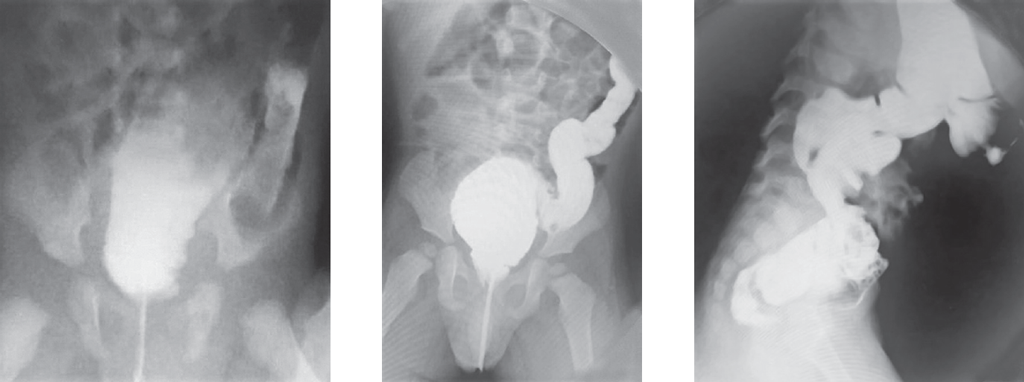

Болезнь Гиршпрунга, как правило, проявляется в первые дни жизни ребенка. Существование различных форм и вариантов ее проявления является основной причиной того, что у части пациентов заболевание не диагностируется в периоде новорожденности. C 2008 по 2019 г. в Детском городском многопрофильном клиническом специализированном центре высоких медицинских технологий г. Санкт-Петербурга находились на лечении 75 детей разного возраста с различными формами болезни Гиршпрунга. В 21 случае диагноз не был установлен сразу после рождения. У 11 новорожденных симптомы заболевания были неяркими и купировались сразу после опорожнения кишечника. У 2 детей с сопутствующей генетической патологией болезнь Гиршпрунга была заподозрена поздно, в связи с имеющимися особенностями опорожнения кишечника у этой группы больных. У части пациентов заболевание проявилось в виде стойкой задержки стула в более старшем возрасте. В статье приведены клинические примеры основных диагностических ошибок у пациентов с болезнью Гиршпрунга или подозрением на нее. Ошибки диагностики у детей раннего возраста связаны как с отсутствием хирургической настороженности у неонатологов родильных домов и отделений новорожденных, так и неправильной трактовкой клинической и рентгенологической картины. Дети в течение многих лет могут наблюдаться и лечиться у различных специалистов, прежде чем попадут в поле зрения детского хирурга.